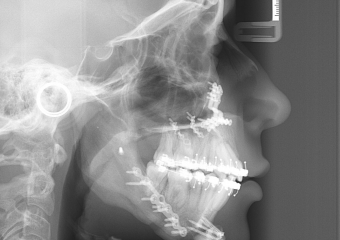

Telerradiografia inicial

Telerradiografia após a cirurgia 2018